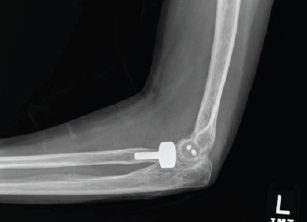

Surgical Treatment of Neglected Elbow Dislocation with the Box-loop Technique: A Case Report

Paulo Henrique Loureiro , Lucas Alves Domiciano Ferreira , Rafael Zonzini Veiga , Victor de Bulhões U. Sechin , Mário Lenza , Sérgio Rowinski

………………………………p.195-200